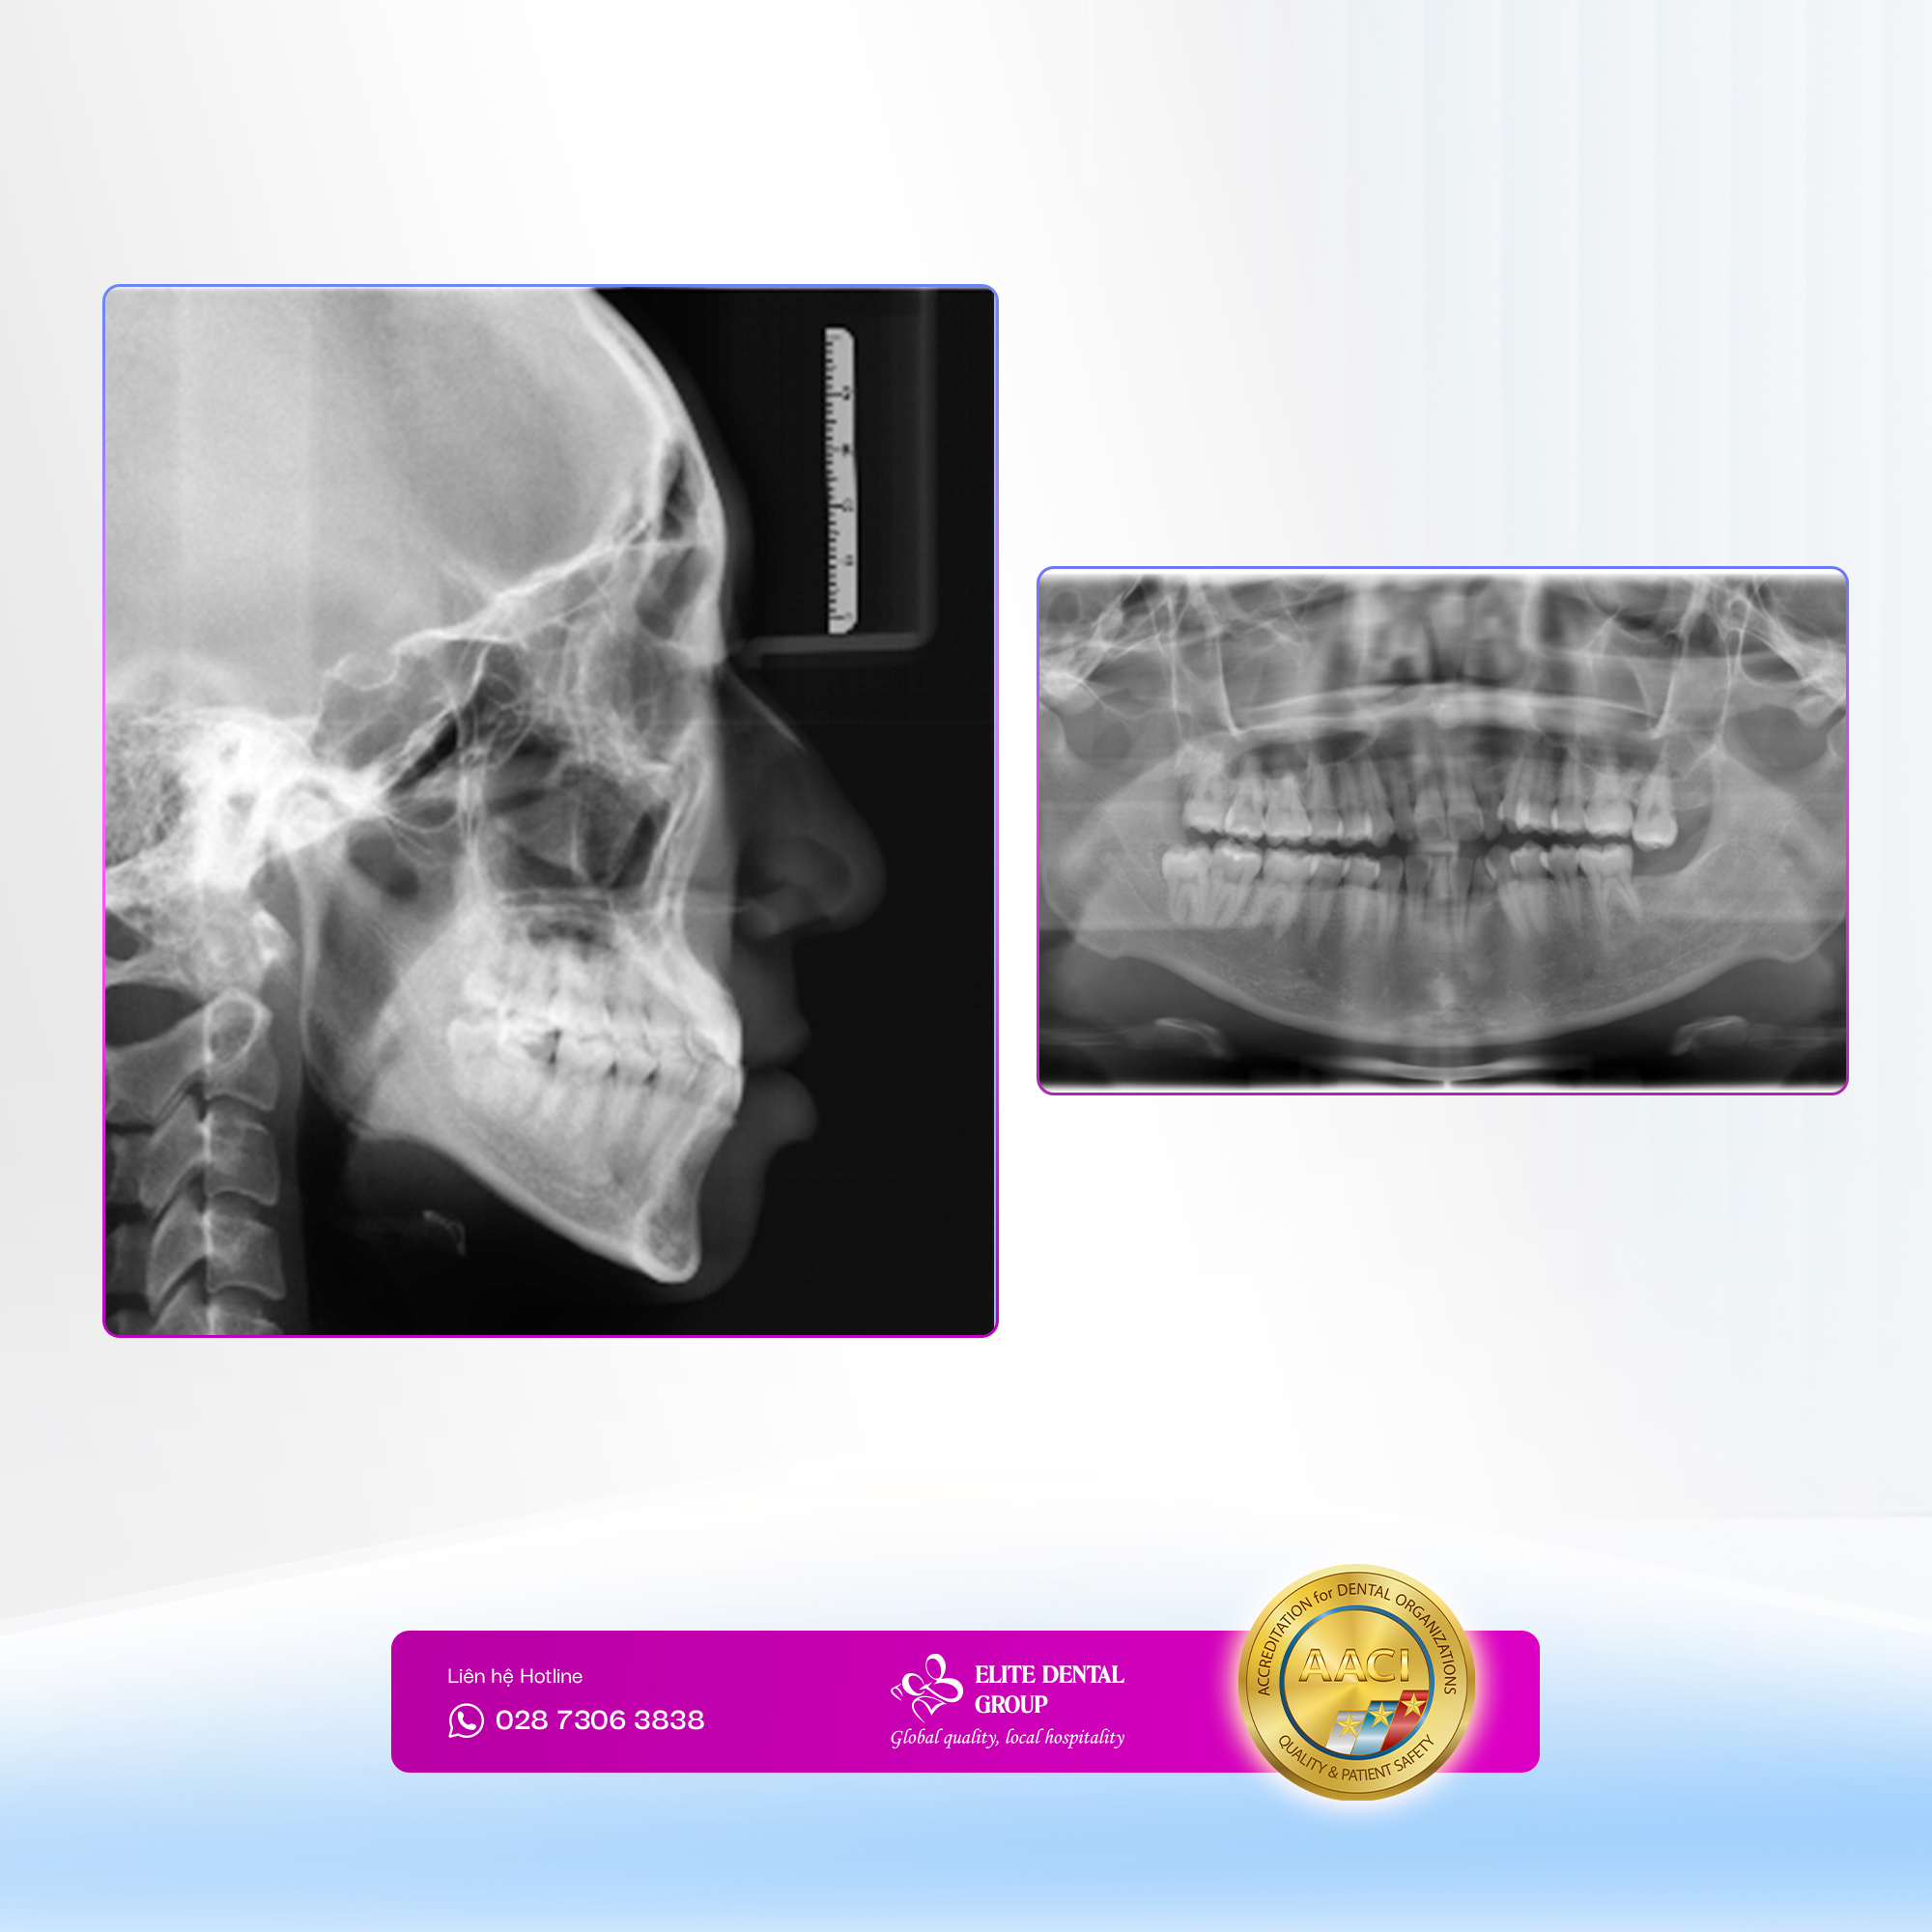

Dựa trên dữ kiện hình ảnh, hình chụp phim và phân tích chuyên sâu về cơ sinh học. ThS. BS Thanh Trúc đã đưa ra một phác đồ niềng răng Invisalign chi tiết cho T.D. Đồng thời theo sát quá trình điều trị để nắm bắt diễn tiến cơ sinh học của từng giai đoạn. Trong quá trình điều trị, chị được hướng dẫn đeo khay đầy đủ, tái khám đúng lịch để hỗ trợ đạt kết quả tối ưu.